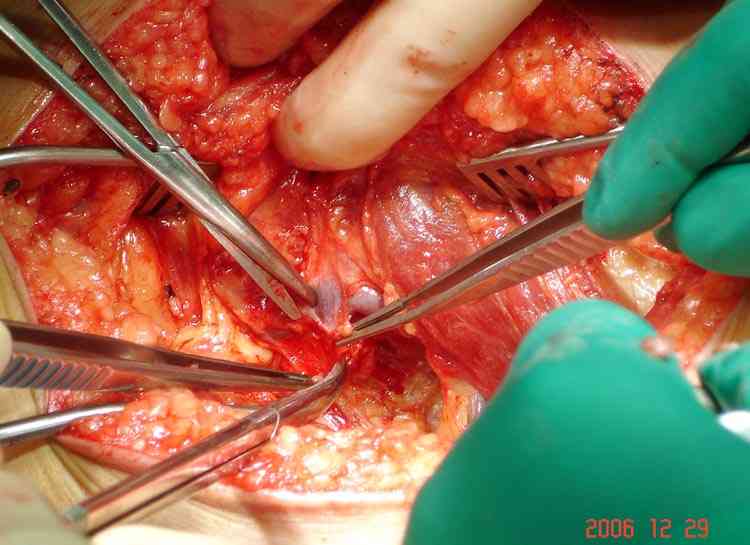

Пару лет назад наблюдал больную 35 лет, физически

здоровую, отслужила в Ираке, жаловалась на слабость в конечности во время физических нагрузок.

Ангиография подтвердила васкулярную аневризму в

результате давления экзостозом. Совместно с сосудистым хирургом была проведена плоскостная резекция с дальнейщим восстановлением сосуда венозным графтом.